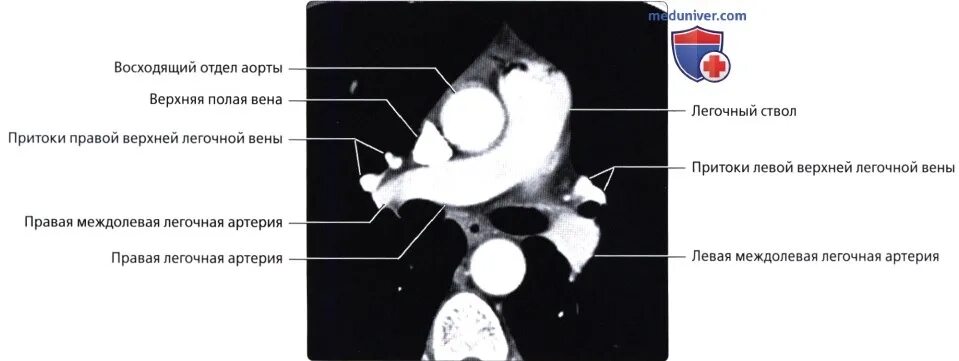

Легочный ствол на кт